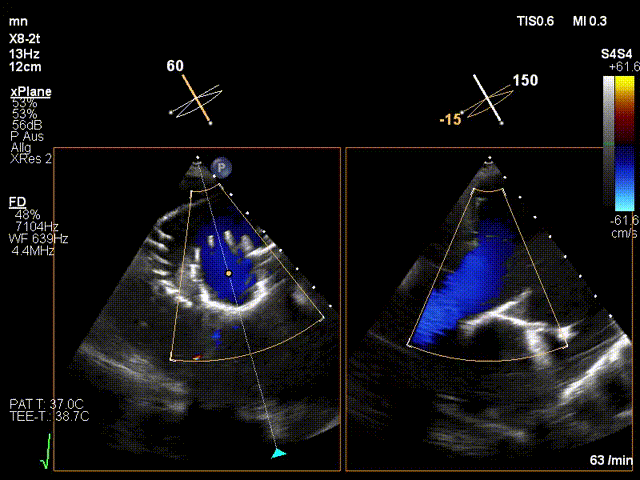

手術(shù)在全麻狀態(tài)下進(jìn)行。在加拿大圣保羅醫(yī)院的Anson Cheung教授的指導(dǎo)參與下,術(shù)者采用經(jīng)右側(cè)頸靜脈入路的方式將輸送器送入患者心臟內(nèi),在TEE及DSA引導(dǎo)下調(diào)整輸送器頭端角度,使得輸送器與三尖瓣瓣環(huán)平面垂直。在輸送器進(jìn)入右心室后釋放室間隔錨定裝置,而后釋放瓣葉夾持件(2個(gè)耳片結(jié)構(gòu))成垂直狀態(tài)。在TEE及DSA確定夾持件固定至三尖瓣葉根部且位于右室側(cè)后釋放人工瓣心房側(cè)盤片。隨后調(diào)整瓣膜同軸性以及室間隔錨定件位置(貼合室間隔),前推藏針管并固定,進(jìn)而釋放室間隔錨定裝置,并再次確認(rèn)瓣膜位置、穩(wěn)定性及同軸性,合攏輸送鞘后撤出輸送器,完成LuX-Valve Plus人工三尖瓣瓣膜的植入。

LuX-Valve Plus經(jīng)血管三尖瓣置換系統(tǒng)本次“出海”圓滿完成,術(shù)后Jörg Hausleiter教授對(duì)LuX-Valve Plus經(jīng)血管三尖瓣置換系統(tǒng)的器械性能和治療效果大為稱贊,認(rèn)為LuX-Valve Plus的手術(shù)體驗(yàn)非常好。術(shù)后即刻超聲顯示三尖瓣反流消失,血流動(dòng)力學(xué)改善顯著,患者恢復(fù)快。Anson Cheung教授也肯定了LuX-Valve Plus術(shù)中操作的便捷性,認(rèn)為LuX-Valve Plus容錯(cuò)率高,對(duì)術(shù)中影像的依賴較小,后期希望可以更多的應(yīng)用LuX-Valve Plus三尖瓣置換系統(tǒng)于臨床實(shí)踐,讓更多的三尖瓣重度反流患者盡早獲益,改善預(yù)后。